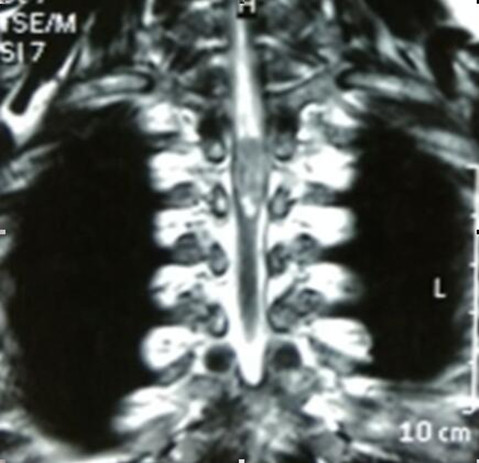

脊髓占位(胸3椎体水平)病变切除术

吴先生65岁,两年前无明显诱因出现双下肢麻木的症状,自行口服药物治疗无明显效果。入院前双下肢略肿胀。吴先生及家人慕名来我院就诊,行MRI检查示:“T3椎体水平脊髓内占位。”入院后查体及辅助检后,临床诊断为:脊髓占位性病变、颈椎病。于4月8日行脊髓探查、病变切除术。目前,吴先生切口愈合良好,肢体活动自如,生活完全自理。

手术难度:因患者为脊髓占位性病变,故手术需切开硬膜囊,探查脊髓,术中操作必须谨慎,若损伤脊髓可导致该节段以下的肢体运动、感觉障碍或瘫痪,若损伤神经根可导致单侧肢体运动、感觉障碍或丧失,需术中积极保护脊髓及神经根,手术风险极大。

术前胸椎MRI